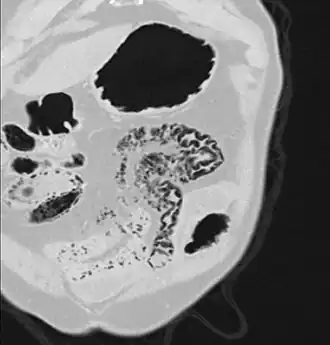

Close-up of intestine of infant showing necrosis and pneumatosis intestinalis (autopsy)

Differential diagnosisnecrotizing enterocolitis